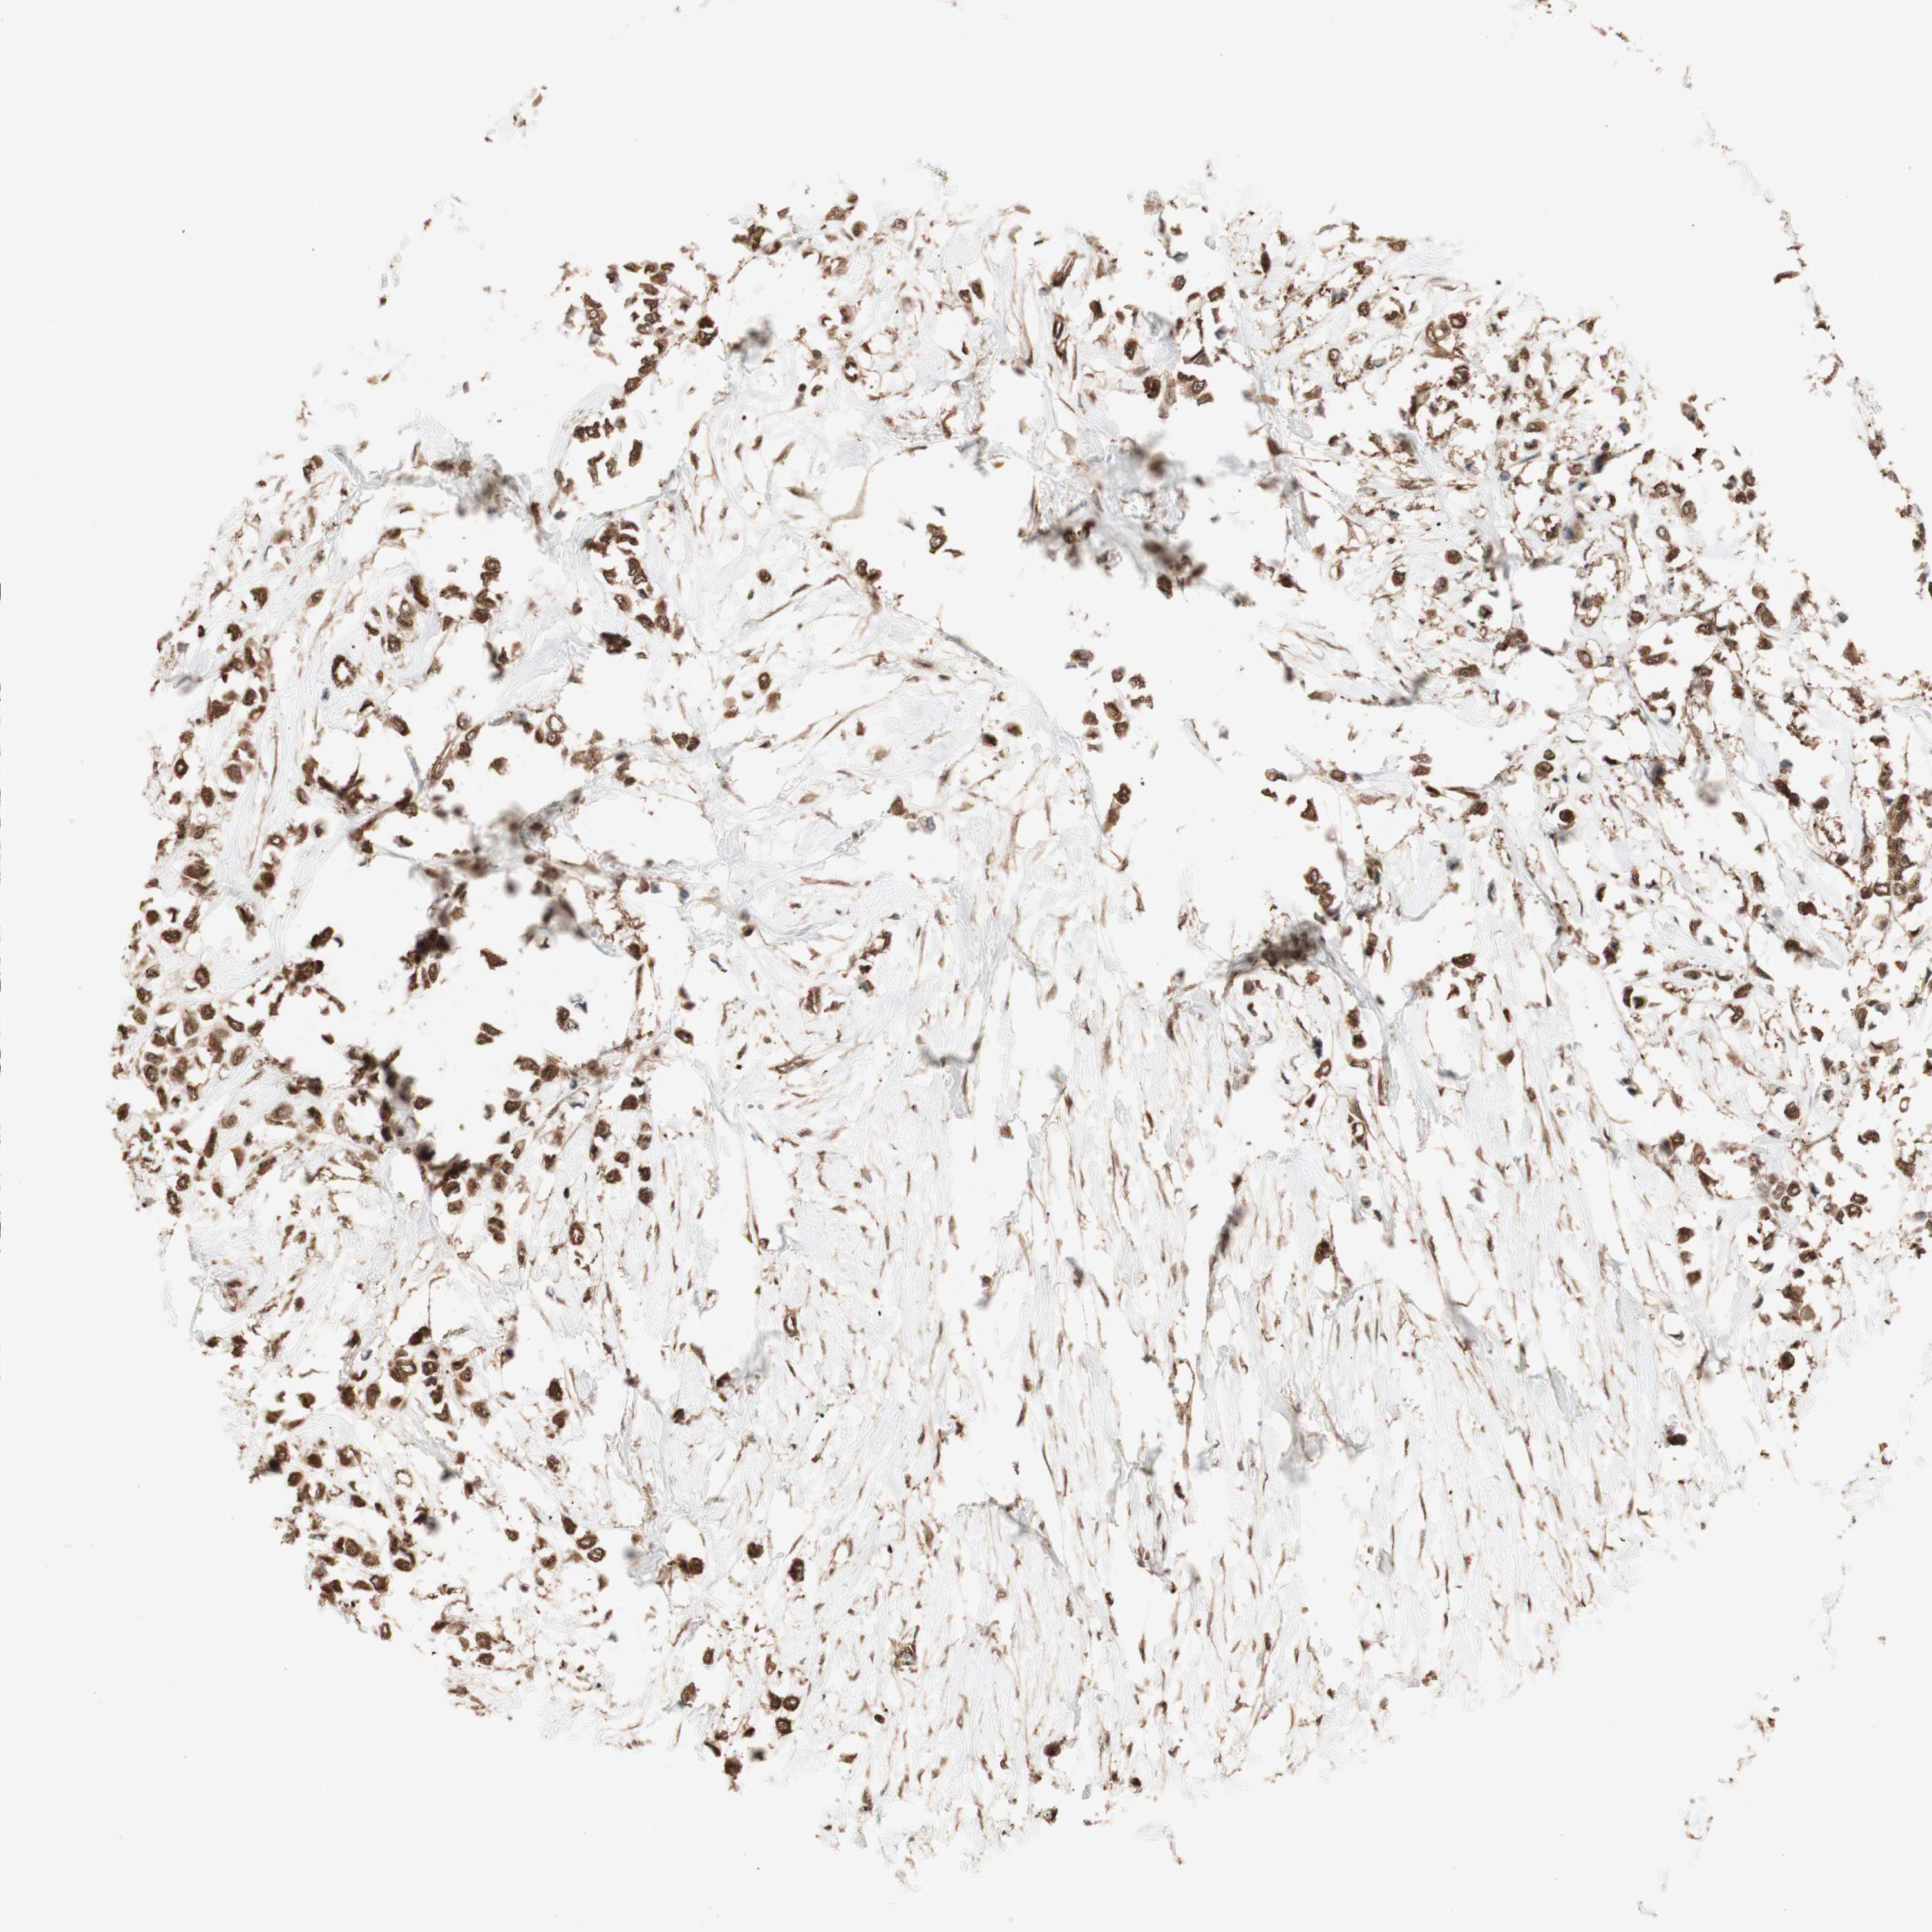

BRCA TCGA BRCA VALIDATION PROTEIN EXPRESSION